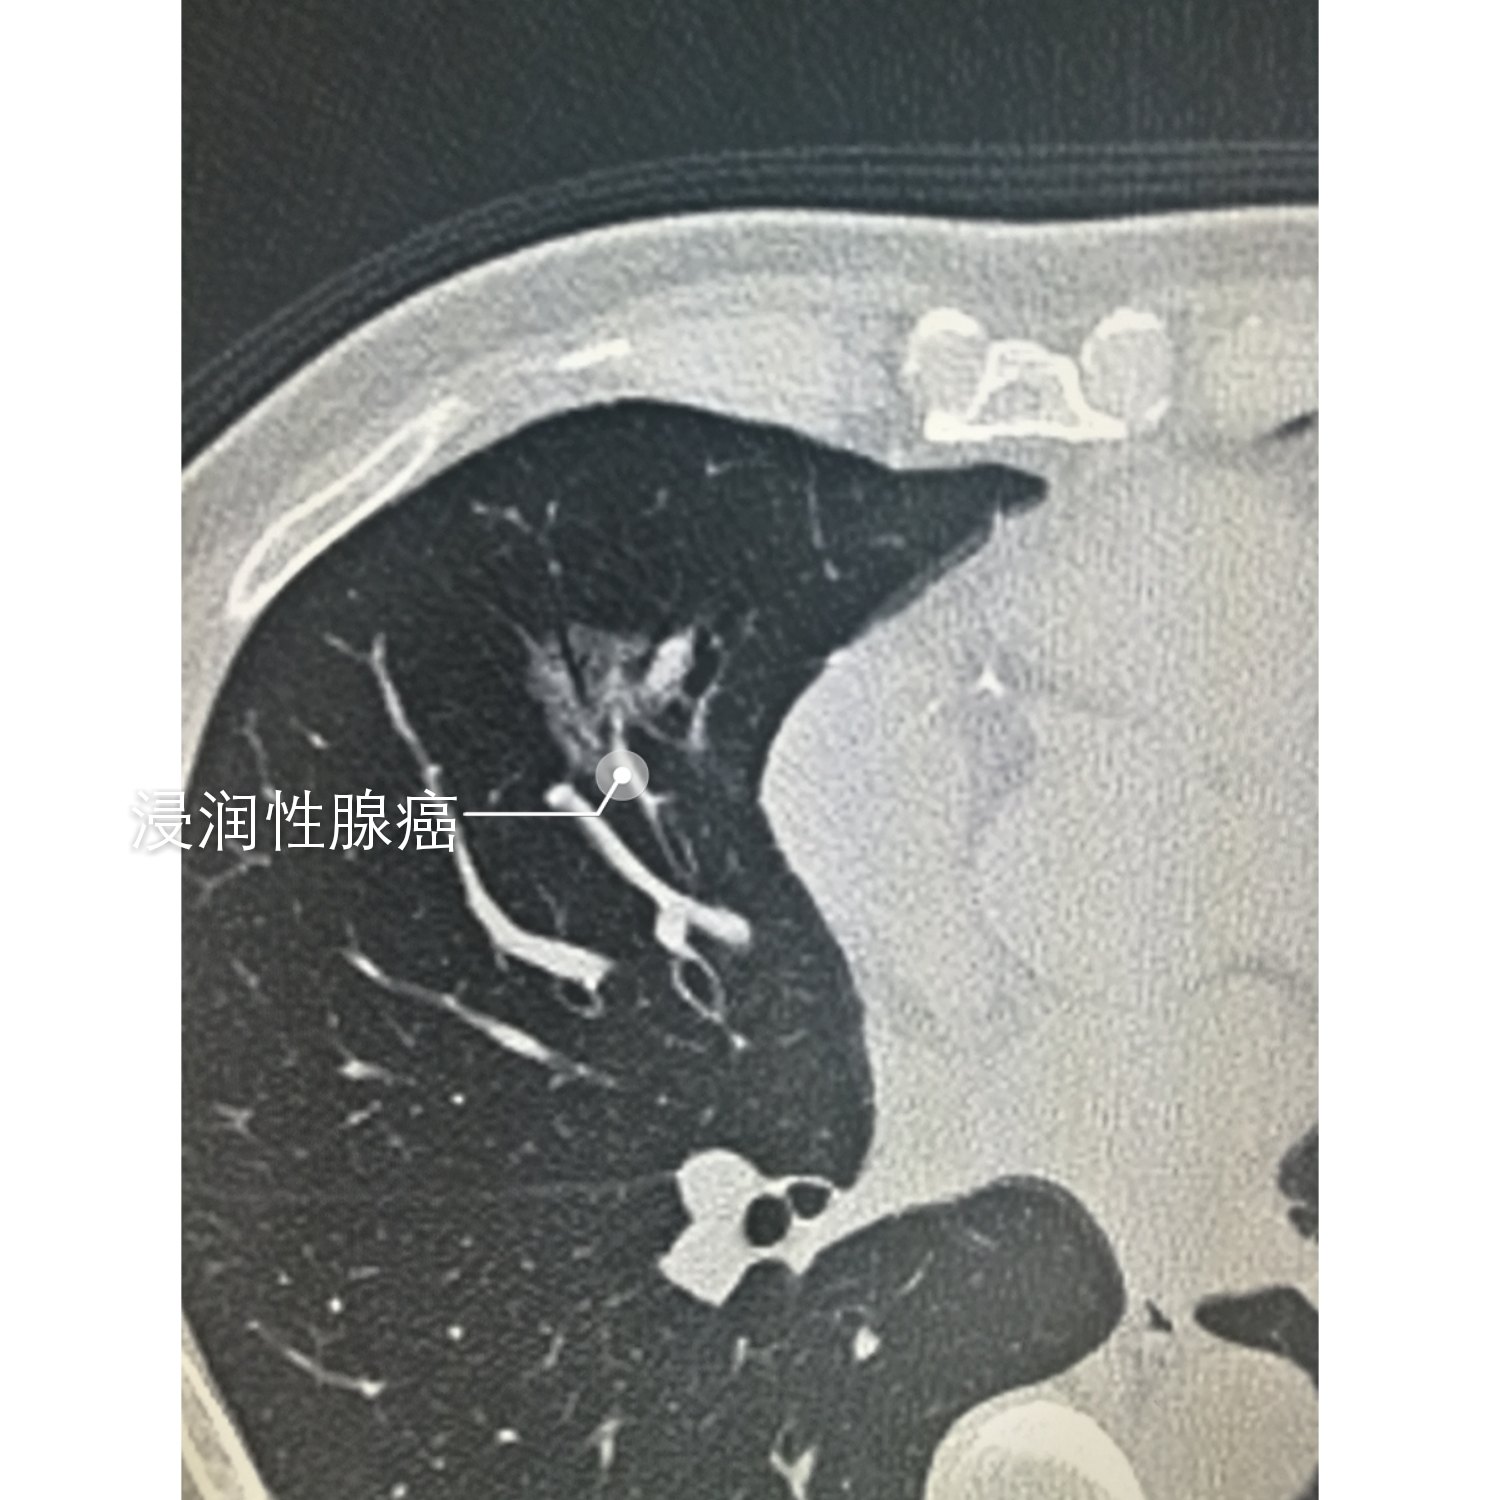

胸廊对称,左上肺磨玻璃病灶,形态不规则,边缘尚清,其规格16.6X11.4mm,其内密度欠均匀,局部胸膜粘连,

两肺上叶多发磨玻璃结节。左肺有个结节毛刺状,有数据报道出来一般不规则密度的结节恶性的可能性比较大

1.左肺下叶不规则结节 2.右肺上叶后段磨玻璃密度结节,考虑恶性病变可能性大。3.右肺上叶后段实性结节影,

以GGO为主要特点的肺部结节称为磨玻璃结节(GGN)。磨玻璃结节也称毛玻璃结节,是肺结节的一种表现形式。从

元芳,多数磨玻璃结节是比较典型的病例,多数纯磨玻璃结节的特点的是,病灶成形,边缘光整。有些少见的磨